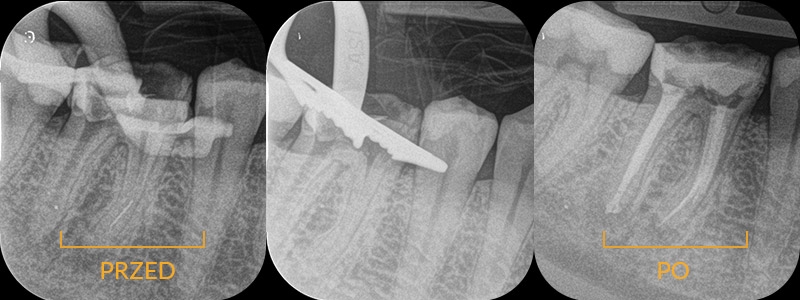

Pacjent zgłosił się do Luxdentica z poważnym problemem - w wyniku wypadku uszkodził żuchwę i kilka przednich zębów. Dzięki współpracy periodontologa, chirurga, a także dzięki leczeniu kanałowemu nie stracił żadnego zęba, chociaż na początku sytuacja wskazywała na konieczność usunięcia 3 siekaczy.